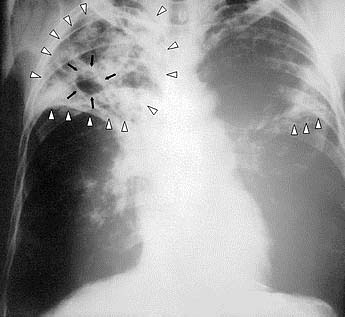

Hình 2: X quang của bịnh nhân bị lao phổi (pulmonary tuberculosis). Các mũi tên trắng chỉ vùng "nám phổi"(pulmonary opacities), mũi tên đen chỉ nơi phổi bên phải bị lũng (cavity).(Source: wikipedia)

Lao được hiểu theo nghĩa phổ thông là bịnh lao (tuberculosis), do con vi khuẩn hình que (bacillus), được bác sĩ Robert Koch người Đức, tìm ra năm 1882. Về phần "cổ" có nghĩa là bịnh sưng bụng do ứ nước (ascites), trong chữ Hán "cổ" viết gần giống như chữ cổ nghĩa là cái trống, không biết có phải người xưa thấy cái bụng báng nước giống cái trống hay không. Một số tác giả tiếng Việt giải thích là xơ gan cổ trướng, và xem chữ “cổ” ở đây có nghĩa là xơ gan (cirrhosis). Về chữ "lại", đa số các bài viết từ Việt Nam giải thích là ung thư (cancer). Vậy thì thông thường, nan y tứ chứng mà chúng ta bàn ở đây là bịnh Hansen , bịnh lao, bịnh xơ gan, và bịnh ung thư.

Cuối cùng, theo nghĩa chữ Hán, "lao" có nghĩa là hao mòn. Bịnh lao do Mycobacterium tuberculosis với những triệu chứng đặc thù như sưng phổi (pneumonia), hang trong phổi (pulmonary cavities), sưng màng óc (meningitis), vv là những ý niệm của y khoa thời thế kỷ 20 trở đi. Lao theo nghĩa chung chung là "hao mòn" có thể do nhiễm trùng khác, ung thư, bịnh thần kinh đúng là nan y nếu không có những phương tiện chữa trị theo khoa học hiện đại. Tuy nhiên , theo tôi nghĩ, đừng hiểu lầm các cụ ngày xưa, và gán nghĩa mới cho lời người xưa.